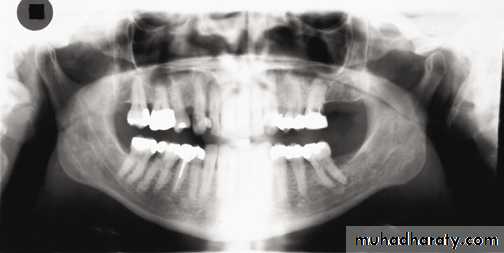

In a good panoramic radiograph:

The mandible is “U” shaped.The condyles are positioned about equal distance from the inside edges of the image and 1⁄3 of the way down from the top edge of the image.

The occlusal plane exhibits a slight curve or “smile line,” upwards.

The roots of the maxillary and mandibular anterior teeth are readily visible with minimal distortion.

Magnification is equal on both sides of the midline.

1, Mandibular condyle. 2, Articular eminence. 3, Coronoid process of mandible superimposed on zygomatic arch. 4, Posterior wall of maxillary sinus. 5, Posterior wall of zygomatic process of maxilla. 6, Hard palate. 7, Nasal septum. 8, Tip of nose. 9, Dorsum of tongue. 10, Hyoid superimposed over inferior border of mandible. 11, Inferior border of maxillary sinus. 12, Image of cervical spine. 13, Medial border of maxillary sinus. 14, Infraorbital canal. 15, Infraorbital rim. 16, Pterygomaxillary fissure. 17, Anterior border of the pterygoid plates. 18, Lateral pterygoid plate superimposed over soft palate and coronoid process of mandible. 19, Ear lobe. 20, Inferior border of mandibular canal. 21, Mental foramen. 22, Posterior wall of nasopharynx. 23, Inferior border of mandible superimposed from opposite side. 24, Soft palate over mandibular foramen of mandible.